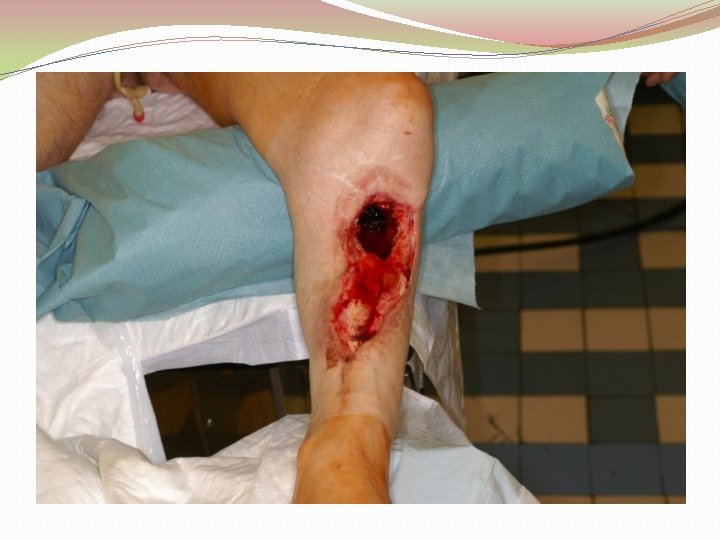

Osteomielīta komplikācijas �Agrīnās: �Sepsis �Abscess �Septisks artrīts �Septiska pneimonija �Plaušu artērijas trombembolija �Perikardīts Robert B. Salter Textbook of disorders and injuries of muskuloskeletal system 3 th edition

Osteomielīta komplikācijas �Vēlīnās: �Pataloģisks lūzums �Locītavas kontraktūra �Kavēta kaula augšanas (bērniem) �Amiloidoze �Plakanšūnu vēzis (Squamous-cell carcinoma) - 0, 2 -1, 7% Robert S. Kirsner, James Spencer, Vincent Falanga, Larry E. Garland, Francisco A. Kerdel Squamous Cell Carcinoma Arising in Osteomyelitis and Chronic Wounds, Dermatological Surgery 1996: 22: 1015 -1018

Ķirurģiska ārstēšana Osteomielīta pacientiem jāveic radikāls debridement ķirurģiski, kas ietver visu procesā iesaistīto audu rezekciju: �Mīksto audu rētas rezekcija �Cīpslu kalcinātu rezekcija �Distantu sekvestru rezekcija �Kaula rezekcija līdz vizuāli veseliem audiem – readzama punktveida asiņošana ´Paprika sign’. Bogdan Maciuceanu, Lucian Jiga, Alexandru Nistor, Jenel Marian Pastrascu, Mihail Ionac Chronic Osteomyelitis of Long Bones Timisoaral Medical Jornal, 2005